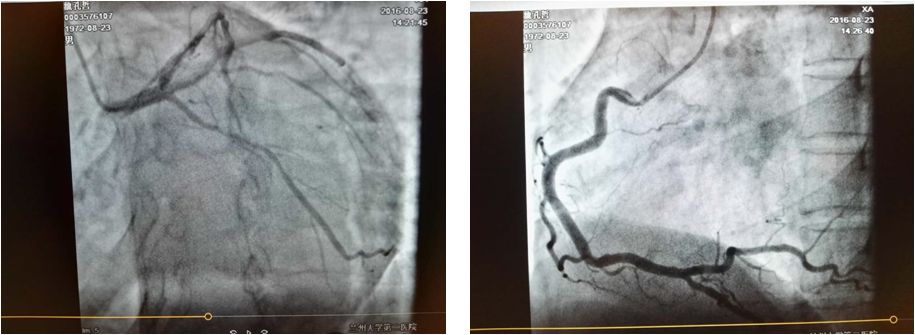

冠脉造影见:LM未见异常,LAD未见异常,远端血流TIMI 3级;LCX中段20-40%弥漫性狭窄,远端血流TIMI 3级;RCA未见异常。

结论:冠状动脉粥样硬化